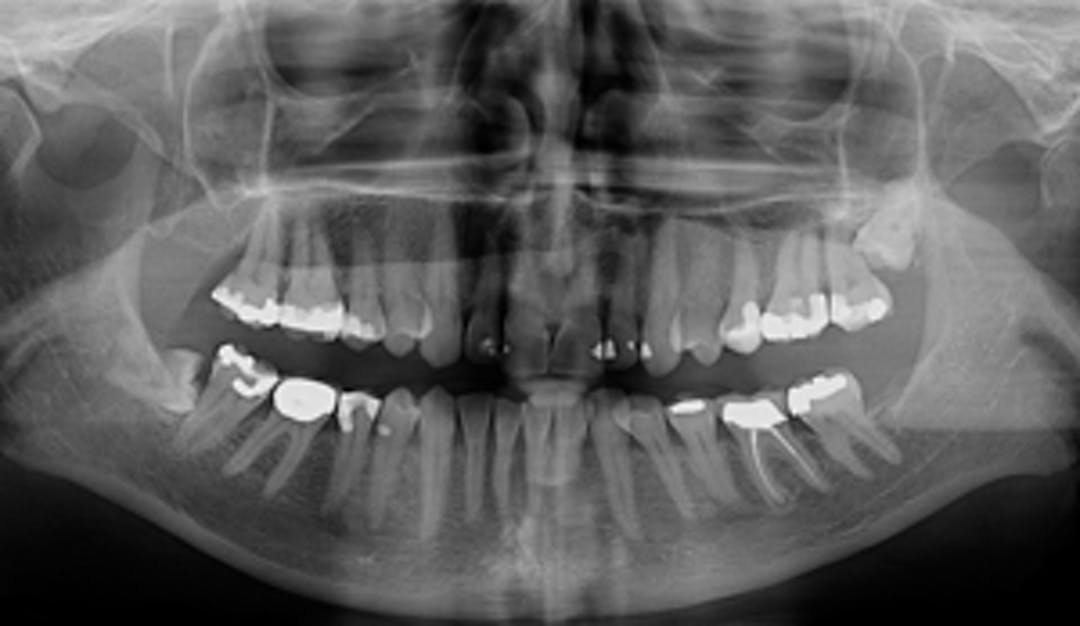

- Kjevecyster: kan være vanskelige å oppdage på annen måte enn ved røntgenbilder.